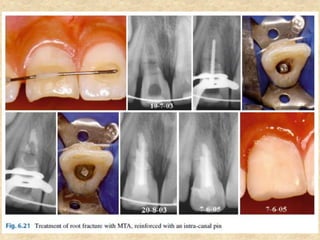

8. Repair of fracture:

pin cemented with MTA

• The canal is instrumented, and then an apical plug with MTA is performed.

A metal pin is selected in order to remain adjusted in the canal, which is

filled with MTA, seating the pin inside. Thus, there is reinforcement for the

root, preventing mobility of the coronary segment.

8. Repair offracture: • The success rate of horizontal root fracture treatment depending on their location (cervical, middle, and apical). The root fracture located in the cervical and middle thirds causes difficulty for treatment because it is difficult for dental immobilization, leading to injury or even preventing the consolidation of the fragments. • For these cases, it is possible to strengthen the tooth with an intra-canal pin cemented with MTA • The canal is instrumented, and then an apical plug with MTA is performed. A metal pin is selected in order to remain adjusted in the canal, which is filled with MTA, seating the pin inside. Thus, there is reinforcement for the root, preventing mobility of the coronary segment. A. Horizontal root fracture: